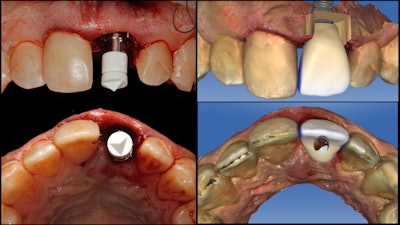

With the implant torqued into place at greater than 50 Ncm, a digital ScanPost (Denstply Sirona) was then placed and imaged to facilitate the design of a Telio CAD (Ivoclar Vivadent) screw-retained immediate provisional using the Cerec Chairside CAD/CAM software (figure 4).

The immediate provisional restoration was manufactured using the Cerec MCXL in-office milling unit (Dentsply Sirona) and delivered in the same visit, with care taken to intentionally undercontour the emergence profile and leave the restoration out of occlusion (figure 5).